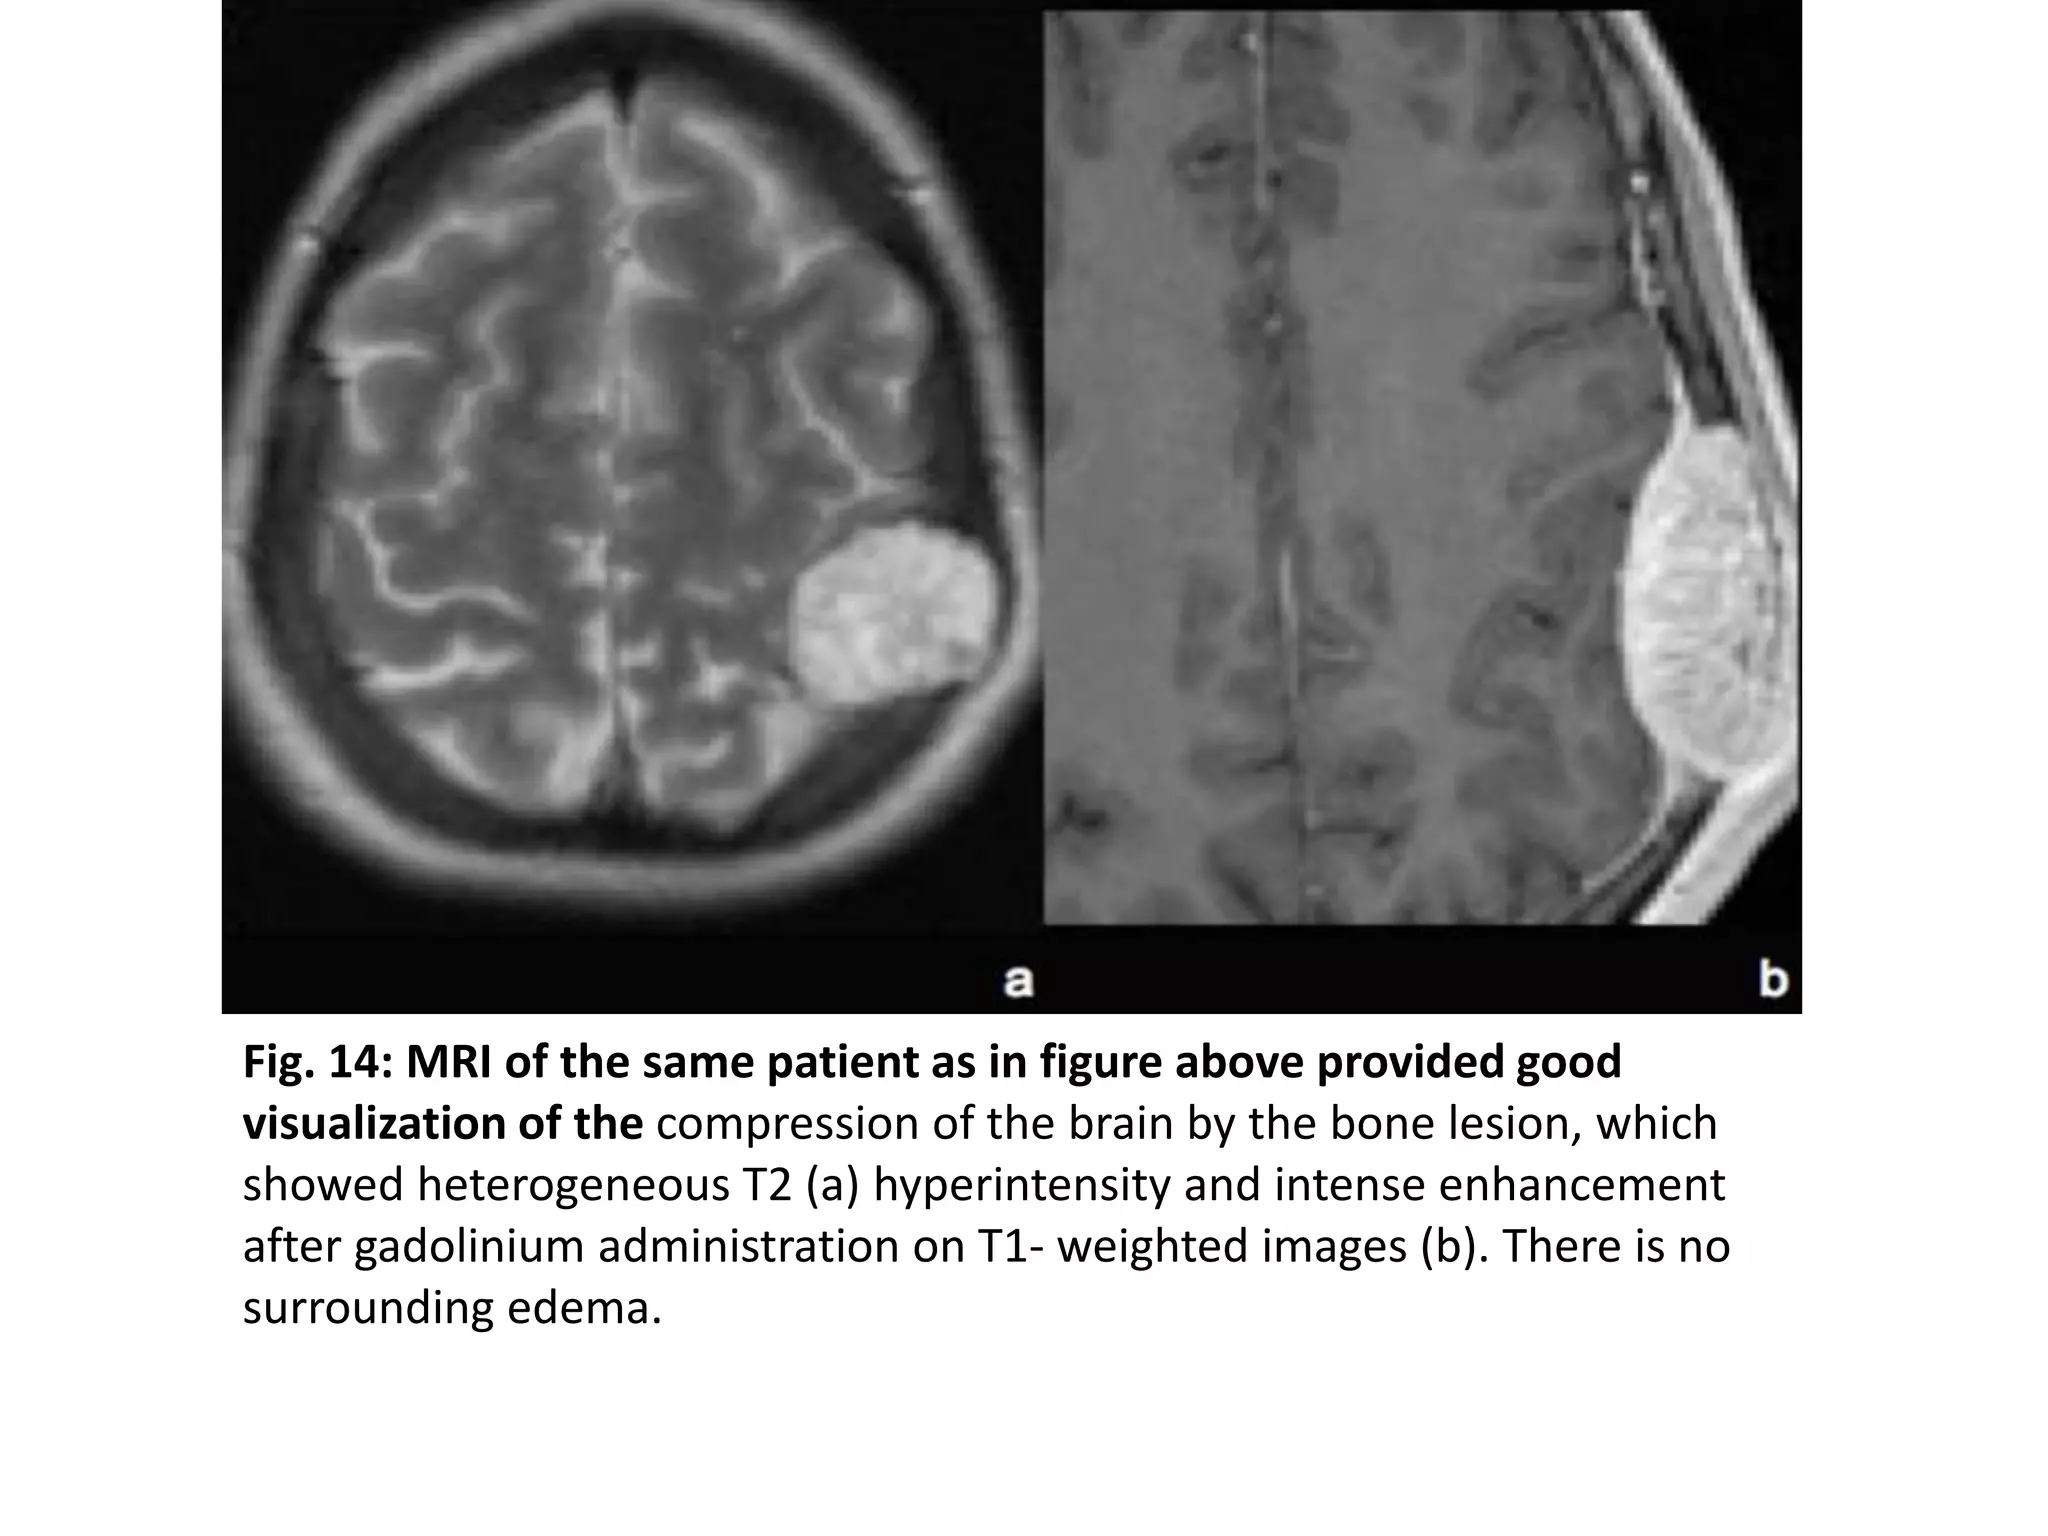

Fig. 14: MRI of the same patient as in figure above provided good

visualization of the compression of the brain by the bone lesion, which

showed heterogeneous T2 (a) hyperintensity and intense enhancement

after gadolinium administration on T1- weighted images (b). There is no

surrounding edema.

Fig. 14: MRIof the same patient as in figure above provided good visualization of the compression of the brain by the bone lesion, which showed heterogeneous T2 (a) hyperintensity and intense enhancement after gadolinium administration on T1- weighted images (b). There is no surrounding edema.